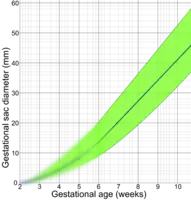

The mean sac diameter[3] can effectively estimate the gestational age[4] between 5 and 6 weeks, with an accuracy of about +/- 5 days.[5]

Crown-rump length before a gestational age of 6 weeks is extrapolated by assuming a gestational sac diameter of 0 at a gestational age of 2 weeks, corresponding to a fertilization age of 0 weeks. This extrapolated part is blurred because of uncertain values. - ↑ Gaillard, Frank. "Mean sac diameter | Radiology Reference Article | Radiopaedia.org". Radiopaedia. Retrieved 2 October 2021.